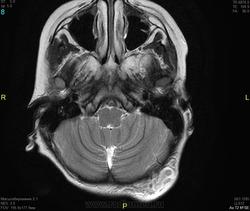

Уважаемые коллеги! Прошу консультативной помощи. Про пациента известно: девочка (7 лет), в анамнезе 2,5 года назад травма головы. Не диагностировалась. Периодически жалобы на болезненность при пальпации затылочной области(((((

Напоминает сосудистую структуру.Может, какая-нибудь лимфангиома?Видела на передней поверхности шеи, на задней - нет.

как будто связь с ликвором имеется.  Дополнил бы венографией, и FatSat"ом ну и контрастом, конечно.

Сегодня в ходе разговора с мамой девочки, выяснилось, что и у мамы есть подобное "образование". С ее слов, несколько лет назад ей делали пункцию для исключения онкологии. Результат пункции: содержится нервная ткань и лимфоциты ( опять же никаких документов я не видела). То есть можно говорить о наследственном характере.

Нейрофиброма вполне может быть. Плексиформная. Проверить на нейрофиброматоз. Я видел такой же структуры и локализации. Пятен на коже нет? Вообще на теле? И нет ли чего похожего в позадиглоточном пространстве?

есть похожее образование в позадиглоточном пространстве)

многоузловое образование  исходящее из задней части предпозвоночного пространства с переходом на подкожную жировую клетчатку головы!шваннома ,нейрофиброма и их злокачественные аналоги